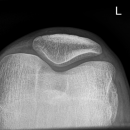

Patella axial (nach Knutsson)

Indikation

Fraktur, Luxation

Qualitätskriterien

Freier Durchblick durch das Femoropatellargelenk und überlagerungsfreie Darstellung der Patella.